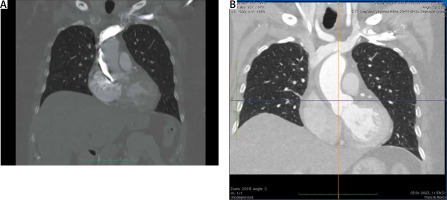

Despite these maneuvers, the no-reflow phenomenon was observed. The emergency computed tomography (CT) angiography revealed a dissection at the right-lateral side of the aorta propagating to the level of the brachiocephalic trunk (Figure 1 A). Of note, the ascending aorta was not dilated, with a maximal diameter of 34 mm.

Figure 1

A – Computed tomographic angiography (CTA) of the ascending aorta after iatrogenic injury; additional contrast in the right lateral side of the aorta fills a false lumen after coronary angiogram. B – CTA of the ascending aorta 3 days after the injury

After stratified risk of early mortality (26.6% according to the EuroSCORE II calculator) was presented, the patient was not convinced of surgery as the only reasonable solution. Eventually, the heart team decided to proceed with conservative management as this high-risk patient presented stable hemodynamics and additionally was unfavorable for aorto-coronary bypass of the RCA (relatively narrow epicardial segments). Pharmacological oral and intravenous blood pressure control and double anti-platelet therapies (clopidogrel + acetylsalicylic acid) were continued. On the second day of hospitalization, the patient developed first degree AV block and needed temporary pacing. Eventually a permanent pacemaker was implanted. Moreover, one cycle of hemodialysis was performed due to acute kidney injury. Follow-up CT angiography performed a few days later showed a hypotensive area in the right lateral side of the aorta (7 mm in thickness) from the level of the aortic valve to the beginning of the brachiocephalic trunk, which might have corresponded to a thrombosed false lumen (Figure 1 B).